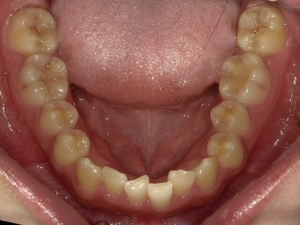

ガタガタとした歯並びや八重歯(叢生)CASE65